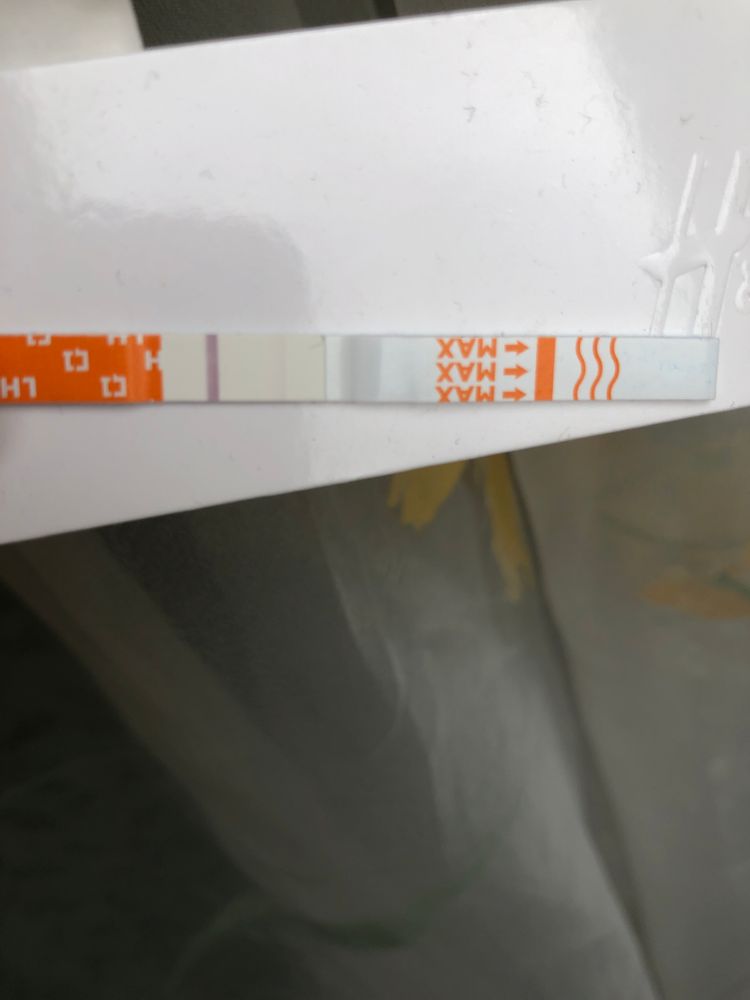

Место под полоску мама чек?

Полоска вроде не там где должна быть?

Полоска вроде не там где должна быть?